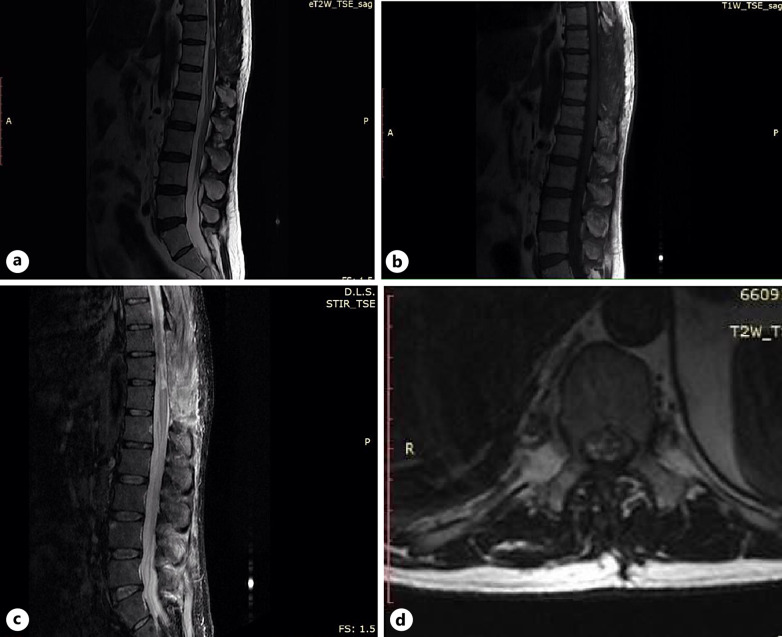

Case presentation: A 55-year-old male was presented with sudden onset of areflexic paraparesis, urinary retention, loss of all sensations below twelve spinal thoracic segments, and severe back pain. This condition necessitated an immediate order of a spinal cord MRI followed by an urgent surgery, which was crucial to save the spinal cord. COVID-19 was confirmed by a positive reverse-transcription-polymerase chain reaction and spinal MRI showed SSDH.